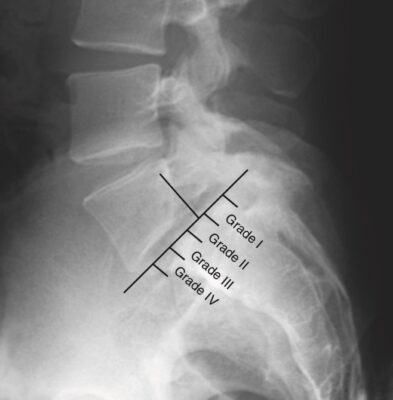

- Trước đây, xét nghiệm tiêu chuẩn để đánh giá một trẻ nghi ngờ bị hở eo là chụp X quang cột sống thắt lưng thẳng, nghiêng, chếch trái và chếch phải. Phim nghiêng phát hiện và đánh giá mức độ trượt đốt sống. Phim chếch có thể cho thấy dấu hiệu “vòng cổ của chú chó Scottie” cổ điển của hở eo. Độ nhạy của phim chếch chỉ đạt tới 33%, và các nghiên cứu gần đây cho thấy các phim chếch ít có giá trị bổ sung cho phim thẳng và nghiêng thông thường.

- Phân độ trượt đốt sống trên X quang: Mức độ trượt đốt sống ra trước được xác định bằng tỷ lệ phần trăm trượt của góc sau – dưới của thân đốt sống ở trên so với mặt trên của thân đốt sống bên dưới (Phân độ Meyer). Trượt ít nhất 5% mới chẩn đoán xác định là có trượt đốt sống.

- Độ I: trượt từ 5% đến 25%;

- Độ II – 26% đến 50%;

- Độ III – 51% đến 75%;

- Độ IV – hơn 75%; và

- Độ V là trật hoàn toàn so với đốt sống lân cận, còn được gọi là sa đốt sống (spondyloptosis).

- Hầu hết các trường hợp (60% đến 75%) là ở độ I; 20% đến 38% ở độ II; và dưới 2% trường hợp trượt đốt sống là ở độ III, IV và V.